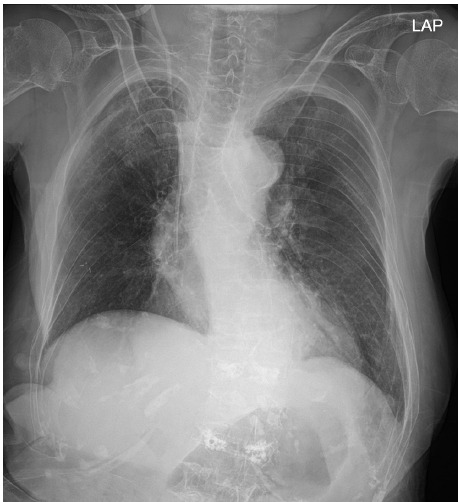

Background: Mounier-Kuhn syndrome (MKS) is a rare disorder characterized by abnormal dilation of the trachea and main bronchi. MKS can be easily missed on chest X-rays, making diagnosis difficult. Under general anesthesia, challenges such as airway leakage or collapse during mechanical ventilation may complicate the achievement of adequate tidal volumes.

Cases: A 94-year-old woman requiring emergency hemiarthroplasty of the hip under general anesthesia was admitted. Preoperative chest X-rays revealed dilation of the trachea and main bronchi, but the patient exhibited no respiratory symptoms. We diagnosed her with MKS and opted for an 8.0-mm-inner-diameter reinforced tracheal tube. We positioned the cuff in the subglottic area, inflating it while monitoring for air leakage. Throughout the surgery, adequate tidal volume was maintained.